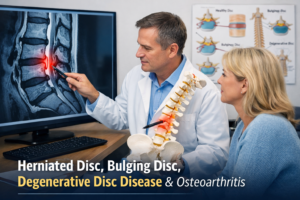

1. Low Back Injuries

Low back pain is one of the most common sports-related complaints. It may stem from disc irritation, facet joint dysfunction, or sacroiliac joint instability. Gonstead care focuses on restoring proper lumbar alignment to reduce nerve irritation and improve core stability.

2. Sciatica and Leg Pain

Sciatica often occurs in athletes who run, lift, or twist frequently. Compression or irritation of lumbar nerves can cause shooting pain, numbness, or weakness down the leg. Precise lumbar and pelvic adjustments are essential for long-term relief.